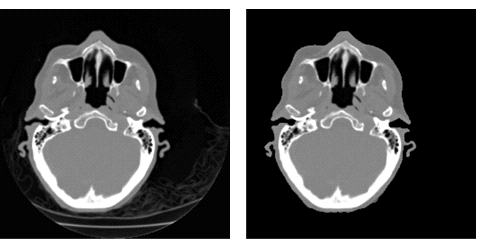

Удаление фоновых элементов изображения с помощью техники сегментирования и выделения сегментов, что особенно полезно для воспроизведения объемного изображения.

res = ImageMultiply[i, SelectComponents[FillingTransform@Binarize[i], "Area", -1]]; GraphicsRow[{i, res}]